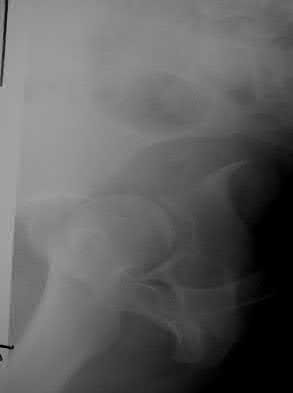

A 76-year-old male community ambulatory presented to clinic complaining of pain in the left groin that has been persistent for the last 8 months. Radiographs obtained from clinic are seen in Figure A. You suspect a femoral neck nonunion and obtain a CT scan which confirmed it. Which of the following statements is true?

A total hip arthroplasty (THA) after nonunion of a femoral neck fracture would provide the best long term outcomes in a 76-year-old male who is a community ambulator.

After nonunion of a femoral neck fracture, hemiarthroplasty and THA are good salvage option for the physiologically older patients. When deciding between these two options, THA is better for active and cognitively intact patients. THA is also indicated in patients with radiographic evidence of degenerative disease about the acetabulum. Hemiarthroplasty is advocated for patients who are older and less active.

Yang et al. retrospectively investigated the risk factors for nonunion in patients treated with cannulated screws. They reviewed 202 patients who had femoral neck fractures and were treated with internal fixation with cannulated screws. They identified that triangle configuration, displaced fracture, borderline or unacceptable reduction, and increased screw shaft subchondral purchase over the femoral neck were all risk factors for nonunion after internal fixation.

Inverted triangle configuration was found to increase rate of union.

Figures and Illustrations:

Figure A is an AP pelvic radiograph demonstrating a nonunion of a femoral neck fracture after suboptimal fixation with 3 cannulated screws in a triangle configuration.